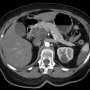

UPDATE: A groundbreaking new drug is giving urgent hope to patients battling stage 4 pancreatic cancer, a disease known for its high mortality rate. Just announced, this treatment could significantly extend life expectancy, transforming the way oncologists approach this deadly cancer.

Irene Blair, a patient diagnosed less than a year ago, faced a devastating prognosis in June 2023, with doctors estimating she had only 6 to 8 months to live. After the rapid advancement of her illness, she became a participant in a promising clinical trial for the new drug, which has shown remarkable results in early testing.

This innovative treatment targets cancer cells more precisely, minimizing damage to healthy tissue and promising improved survival rates. Experts are calling this a potential game-changer in a field where options have been limited for far too long. Patients and families are rallying around this new hope, eager for updates and the possibility of extended lives.

The urgency of the situation cannot be overstated. With pancreatic cancer being the third leading cause of cancer-related deaths globally, advancements in treatment are critical. The new drug is currently undergoing final phases of clinical trials, with results expected to be released within the next few months.